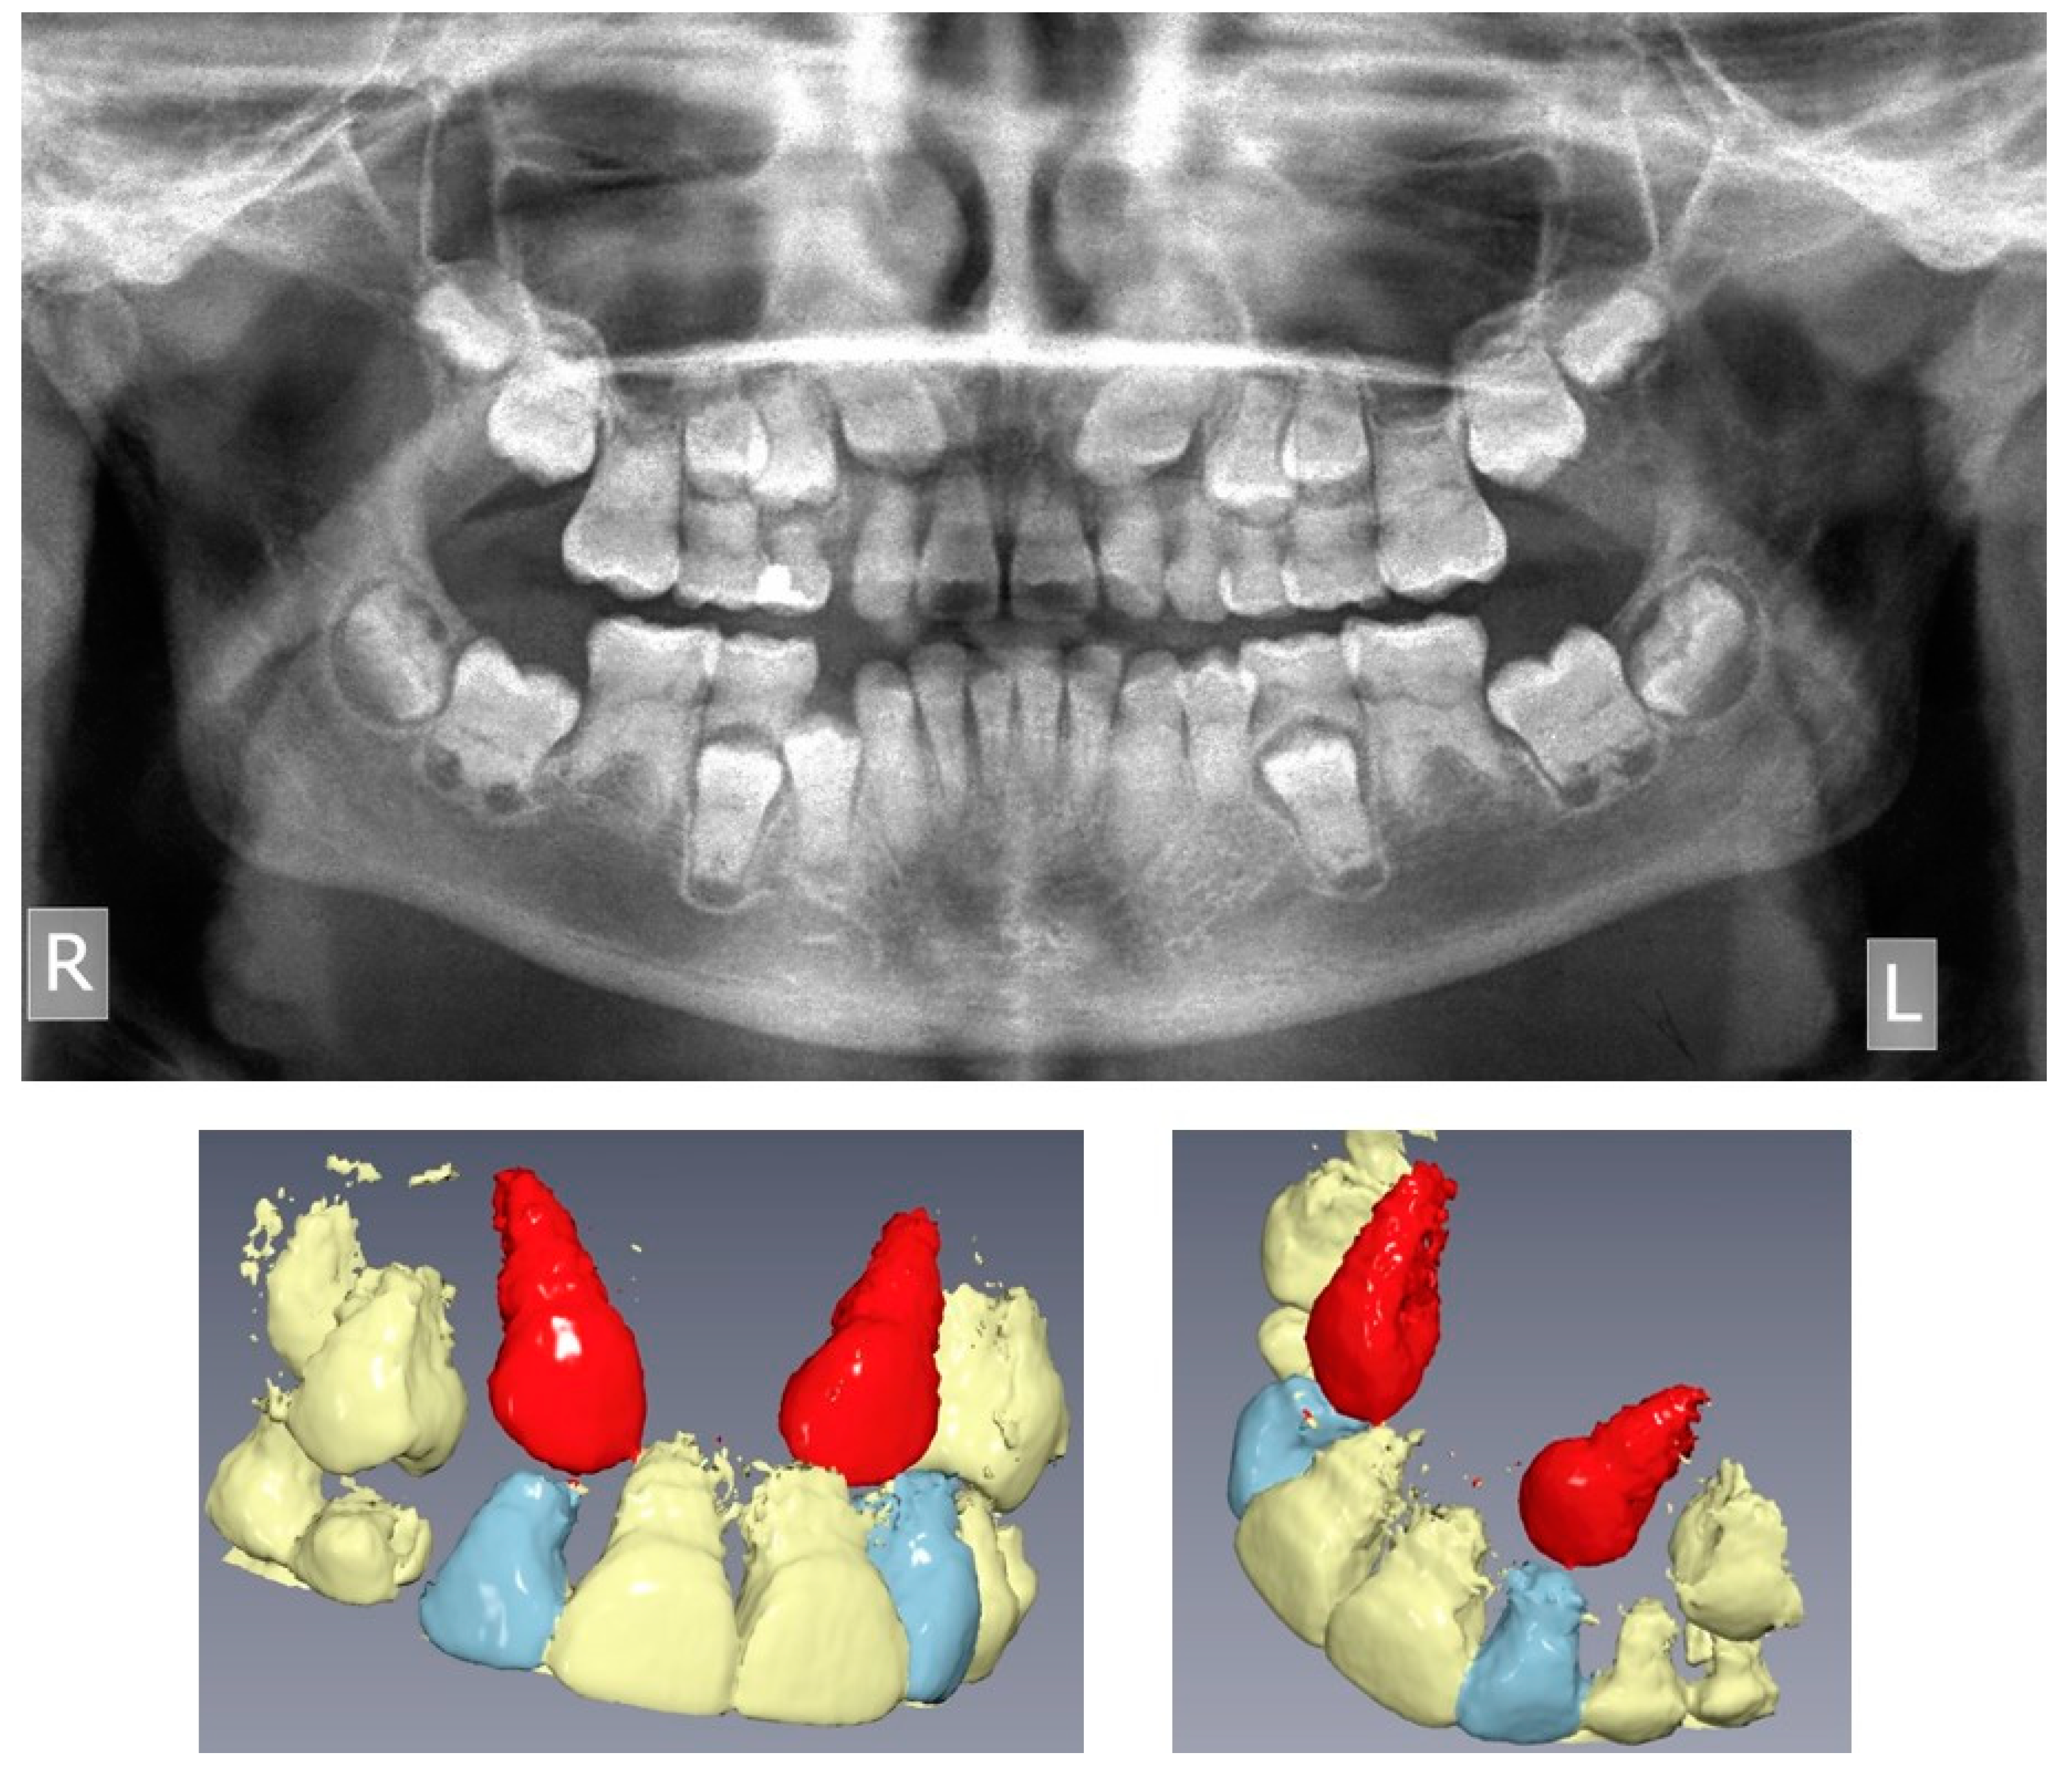

2. Case Presentation

2.1. Clinical Findings and Diagnosis